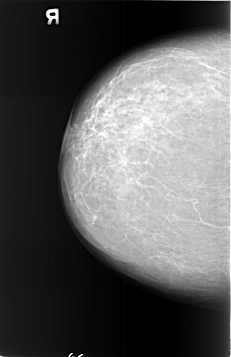

B_3401_1.RIGHT_MLO

RIGHT_MLO LINES 5696 PIXELS_PER_LINE 3704 BITS_PER_PIXEL 12 RESOLUTION 50 NON_OVERLAY